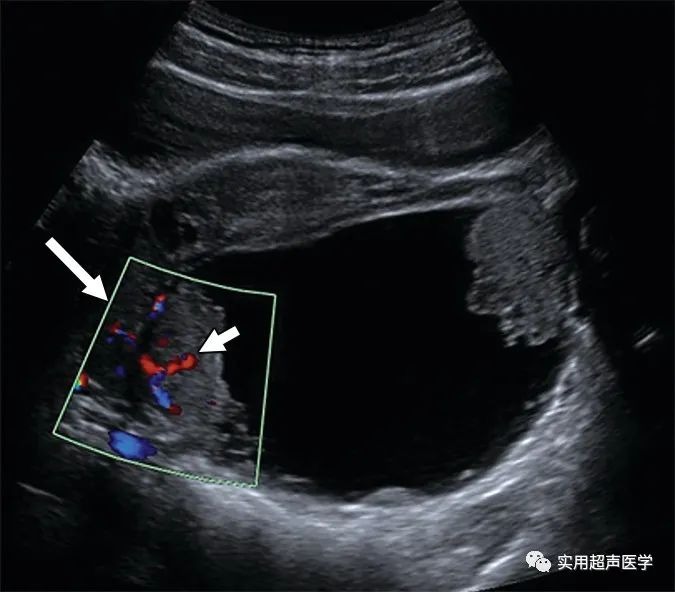

图片30岁孕妇在妊娠13周5天时接受颈项透明层试验,发现单房囊肿有实性成分。具有更大的彩色框(大箭头)的初始彩色多普勒超声图像显示固体成分(小箭头)中没有流动。这可能会导致误解为凝块等碎片。

同一患者彩色多普勒超声图像的彩色框(大箭头)显示确认实体组织的血流(小箭头)。浆液界性肿瘤在胎龄18周时切除。